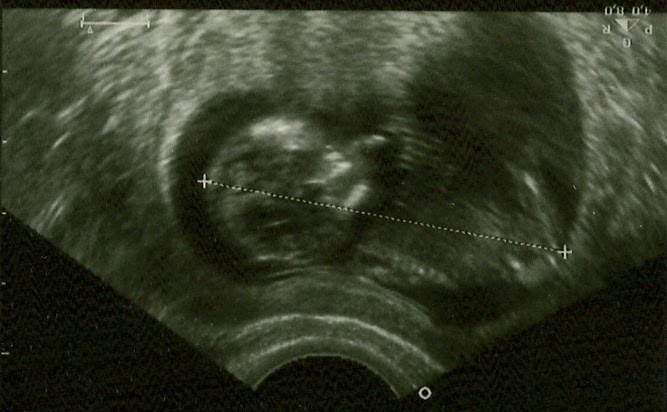

They say that it takes about 4 years to settle in. I think it takes having two kids. Our second is due in November. We are having a girl this time and I think I´m more scared this time. I´m really freaking out about having to put tights on her. I keep thinking about a squid wriggling around and trying to get tights on one of those. I hated putting pantyhose on myself when I was working in Toronto. This is going to be hell! Still, I am pretty excited. When I´m not too exhausted or bitchy. This one has definitely been more difficult. I think excitement got the best of me when I was pregnant with JR. This one is not so new anymore and I´m still working full time in a job that requires a lot of memory which I don´t have these days. IT´s true what they say. Your brains start to fall out when you have kids.